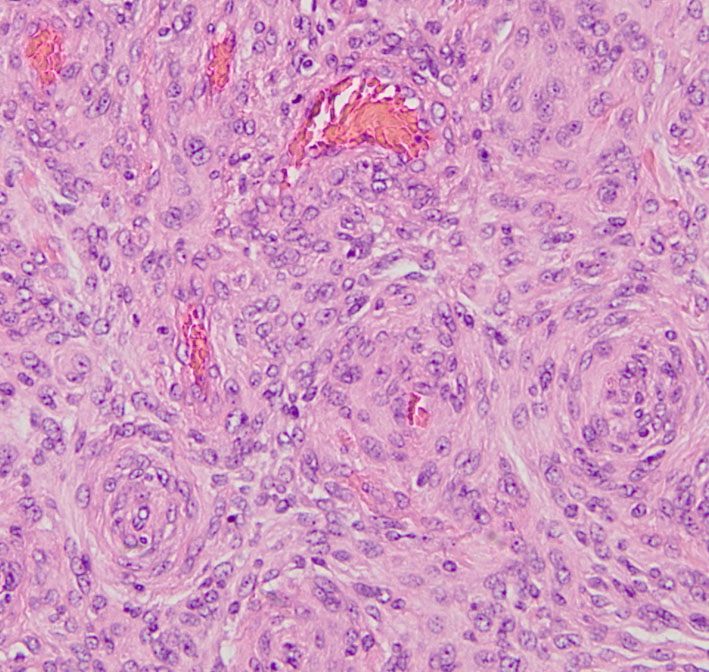

放射線誘発膠芽腫(グリオブラストーマ)

放射線治療10年後です。側脳室の中の腫瘍は小さくなって再発はありませんが,脳幹部と小脳に膠芽腫が発生しました(右側のMRI)。この腫瘍も放射線誘発腫瘍と考えられます。脳幹部の膠芽腫は助かることがない悪性腫瘍です。

松果体のジャーミノーマのために,19歳の時に全脳照射30グレイと松果体局所照射20グレイを受けました。これは28歳の時に発生した右側頭葉の膠芽腫です。この部分には30グレイしか入っていないのですが,2.5グレイという大きな1日線量が用いられていました。またslit-beam rotationという1990年代初頭に用いられた照射方がされています。同じ線量であっても二次ガンを招きやすい照射法というのがあるのかもしれません。